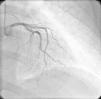

On physical examination she was hemodynamically stable, with no relevant alterations. The 12-lead electrocardiogram (ECG) showed sinus rhythm and ST-segment depression in V4, with negative T waves in V4-V5 and flattened T waves in V6 and frontal leads (Figure 1). Laboratory tests revealed hemoglobin 11.3g/dl, erythrocyte sedimentation rate 84mm, C-reactive protein 6.14mg/dl, troponin I 1.89ng/dl (rising slightly on the second assessment to 2.02ng/dl) and CK-MB 8.4ng/ml. She was therefore admitted to our coronary care unit with a diagnosis of non-ST elevation acute myocardial infarction. Transthoracic echocardiography showed moderate to severe left ventricular systolic dysfunction, with apical akinesia and hypokinesia of the mid-apical segments of the anterior and lateral walls and interventricular septum. As well as these wall motion abnormalities, a large left atrial mass was observed attached to the interatrial septum, coral-like and with a friable appearance, measuring 46mm on its longest axis, the most apical portion of which prolapsed into the left ventricle in diastole over the anterior leaflet of the mitral valve, without causing fixed obstruction to flow in the left ventricular outflow tract (Figure 2). Given the high suspicion of myxoma, transesophageal echocardiography was immediately performed (Figure 3), which confirmed the findings of transthoracic echocardiography. In view of the risk of imminent embolization, the cardiothoracic surgery department at our referral hospital was contacted and accepted our patient after coronary angiography, which revealed no significant lesions (Figure 4).

Coronary angiography is valuable in cases of cardiac myxoma presenting with AMI to screen for coronary disease, especially in patients aged over 40 or with cardiovascular risk factors. Embolization to the anterior descending and circumflex arteries has been reported, but embolization to the right coronary artery is more common, possibly because of the orientation of the right coronary artery ostium relative to aortic flow. In a significant number of cases no coronary lesions are detected on angiography, which may be explained by the high rate of recanalization of coronary emboli from myxomas.6